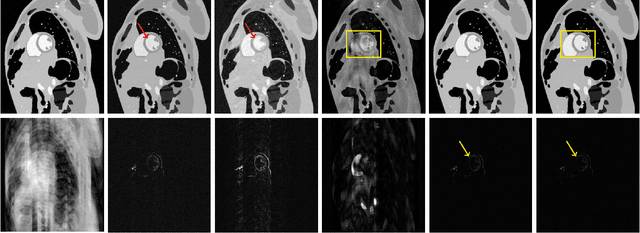

Abstract:This paper establishes a kernel-based framework for reconstructing data on manifolds, tailored to fit the dynamic-(d)MRI-data recovery problem. The proposed methodology exploits simple tangent-space geometries of manifolds in reproducing kernel Hilbert spaces and follows classical kernel-approximation arguments to form the data-recovery task as a bi-linear inverse problem. Departing from mainstream approaches, the proposed methodology uses no training data, employs no graph Laplacian matrix to penalize the optimization task, uses no costly (kernel) pre-imaging step to map feature points back to the input space, and utilizes complex-valued kernel functions to account for k-space data. The framework is validated on synthetically generated dMRI data, where comparisons against state-of-the-art schemes highlight the rich potential of the proposed approach in data-recovery problems.